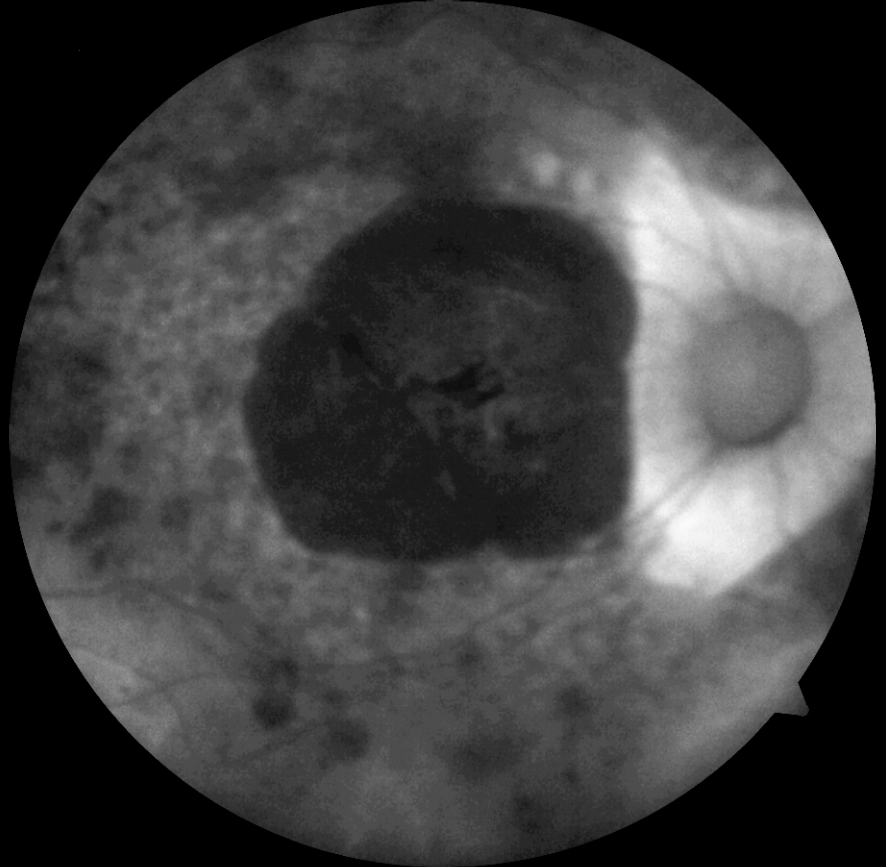

14 yaşındaki erkek hasta bebeklikten bu yana görme kaybı öyküsü ile kliniğimize başvurmuştur. Ailenin tek çocuğudur, anne baba arasında akraba evliliği öyküsü mevcuttur ve her iki gözde görme 1 mps düzeyindedir. Hastanın renkli fundus, FAF ve OCT görüntülerini görmektesiniz. Lütfen cevabınızı aşağıya yazınız.